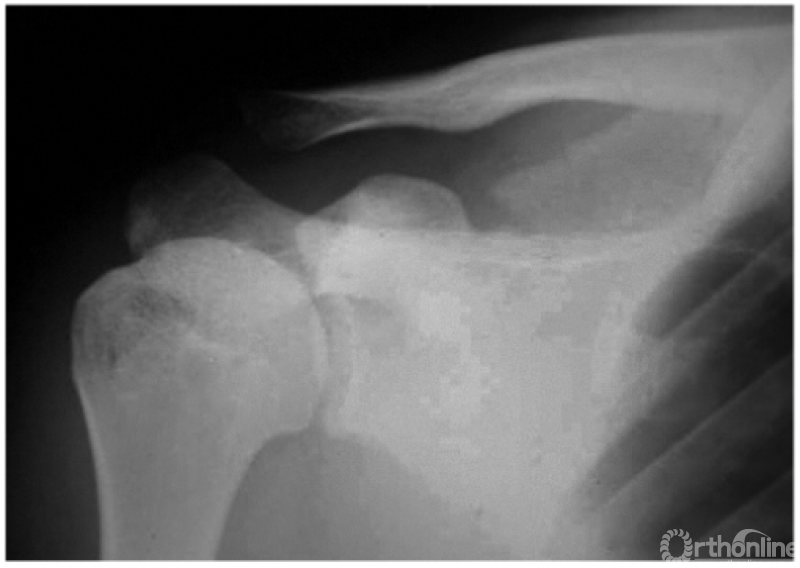

2. 锁骨外段骨折

本例虽系外段骨折,但由于喙锁韧带断裂亦可引起锁骨近折端向后上翘起(图2)。